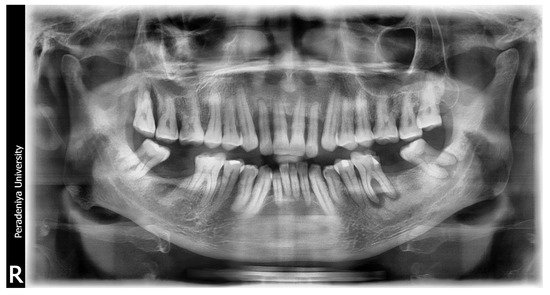

Figure A3.

Sample DPT image 01.

Figure A5.

Sample DPT image 02.